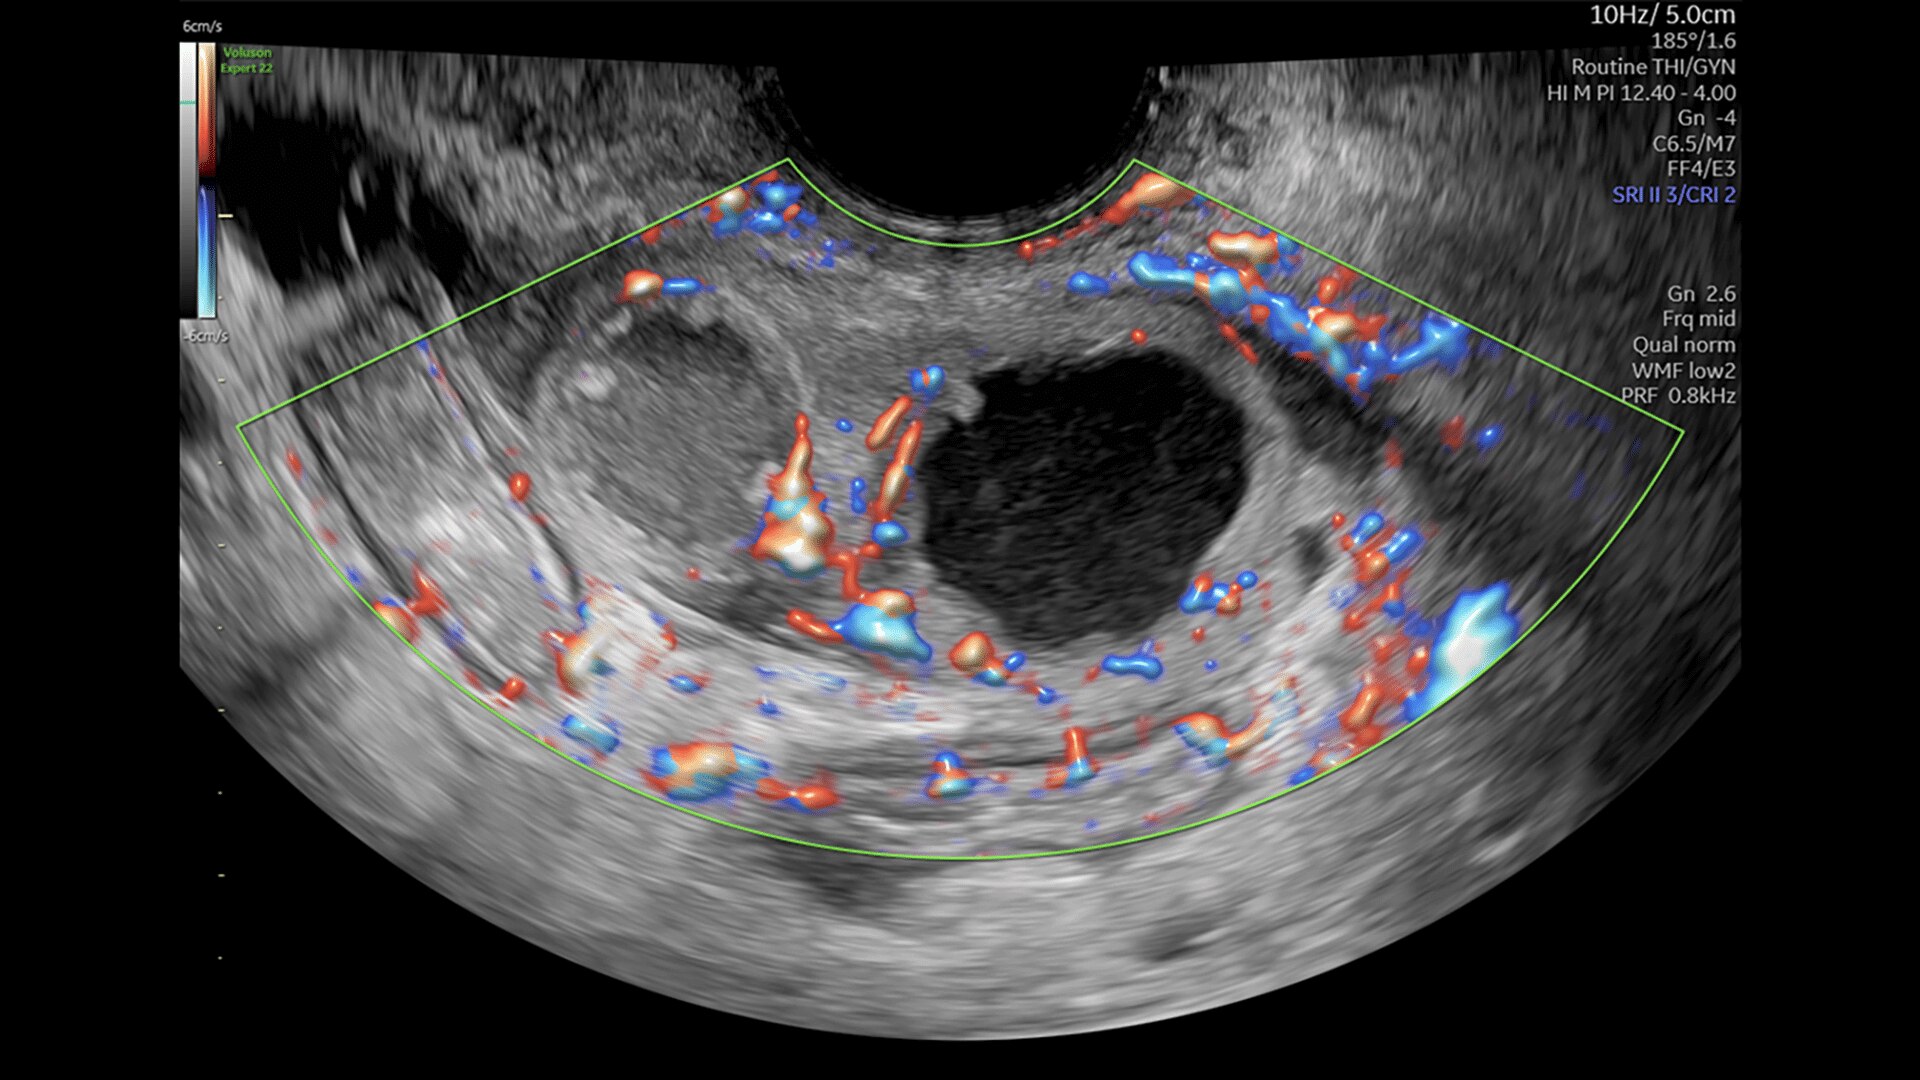

Pelvic Health

Offer patient answers faster with Ai-based automation tools